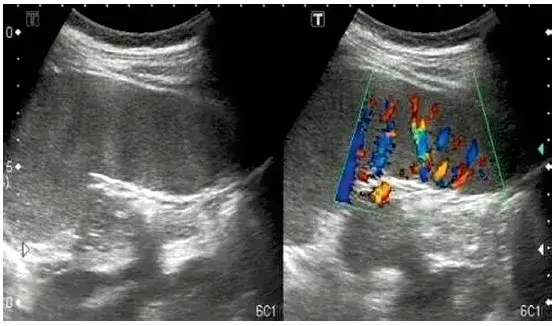

USG jamy brzusznej: bezbolesne badanie, które pokazuje bardzo wiele

Ultrasonografia (USG) jamy brzusznej to podstawowe i najczęściej zlecanie badanie obrazowe w diagnostyce bólu nerek. Jest bezbolesne, nieinwazyjne i łatwo dostępne. Dzięki USG lekarz może ocenić wielkość, kształt i budowę nerek, a także wykryć obecność kamieni, torbieli, guzów, zastoju moczu (np. wodonercza) czy innych nieprawidłowości. To badanie jest niezwykle cenne, ponieważ pozwala szybko zlokalizować problem i często jest pierwszym krokiem do postawienia trafnej diagnozy.